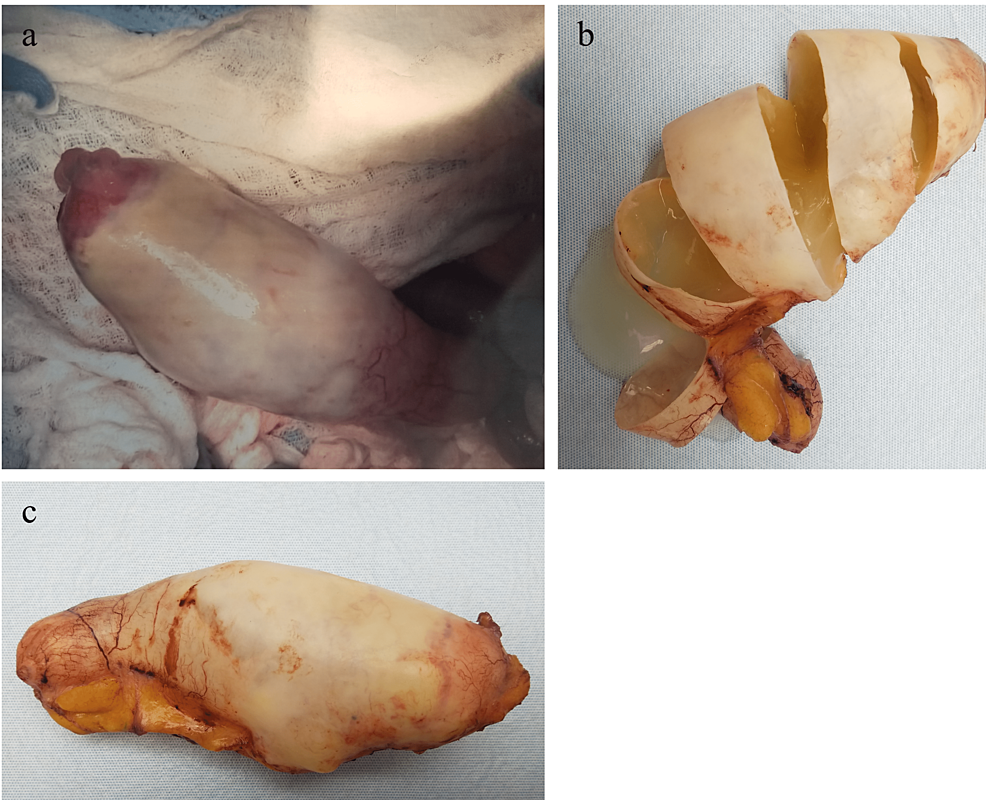

A 79-year-old male presented with three weeks of constipation and a 24-pound weight loss over the past year. He denied any family history of colorectal cancer. He was found to have a RLQ mass on exam. Labs demonstrated elevated carcinoembryonic antigen (CEA) levels. CT abdomen and pelvis with IV contrast demonstrated a 7 cm x 13 cm x 8 cm cystic lesion lying adjacent to the cecum consistent with a fluid-filled appendix. Surgery was recommended to the patient as the standard of care, but the patient refused and requested for non-operative management. The patient was managed non-operatively under the condition that surgery would be strongly advised if the findings did not normalize on follow-up imaging. A repeat CT abdomen and pelvis with IV contrast two months later demonstrated a 7 cm x 12.5 cm x 8 cm cystic lesion with peripheral calcification in the right abdomen and a thickened appendix measuring up to 1 cm without peri-appendiceal stranding. Exploratory laparotomy and appendectomy were performed, during which a large cystic appendiceal tumor was removed. Pathological examination of the appendiceal mass revealed an LAMN with negative margins and pTis (in situ) staging. Given the negative margins with no findings of peritoneal dissemination, appendectomy was deemed acceptable for management. Additionally, because LAMN could present with elevated CEA as a tumor marker and was associated with concurrent gastrointestinal (GI) malignancy, a colonoscopy of the cecum was performed, which was negative for signs of colorectal cancer.

Although LAMN can be generally asymptomatic and stable, it can also lead to a number of serious complications over time [1-3]. LAMN can rupture and disseminate mucin and neoplastic cells into the peritoneal cavity and result in PMP, an intraperitoneal accumulation of mucinous tumors and mucinous ascites that is associated with poor outcomes and high mortality risk [1-3]. Therefore, timely workup and management are essential to prevent progression to PMP and metastasis and improve overall outcome and recovery. Given it can be asymptomatic and have nonspecific findings when symptomatic, imaging is important for the initial detection of a mucinous appendix and surveillance for rupture. When intact, abdominal ultrasound can show a distended cystic appendix with porcelain wall calcification and a lamellated mucinous “onion-skin” appearance, though rupture will show an interruption in the appendiceal wall with leakage, while PMP will show thickening of the peritoneum or omentum, anechoic regions, echogenic foci, and septations [3]. CT can show an enlarged appendix with wall calcifications and thickening, and additionally demonstrate septations, calcified nodules, and liver margin scalloping in PMP (Figures 2–4) [1, 3]. Magnetic resonance imaging (MRI) can show a hyperintense distended appendix and bright mucin appearance on T2-weighted MRI, as well as nodularity on MRI with contrast [3]. A biopsy is not recommended due to perforation risk, though if the lesion has disseminated peritoneally, a biopsy of peritoneal nodules can be helpful for diagnosis [3]. Through these diagnostic measures, they can help to identify mucinous appendices, monitor for rupture, and allow for timely management to reduce the risk of dissemination and progression to PMP.